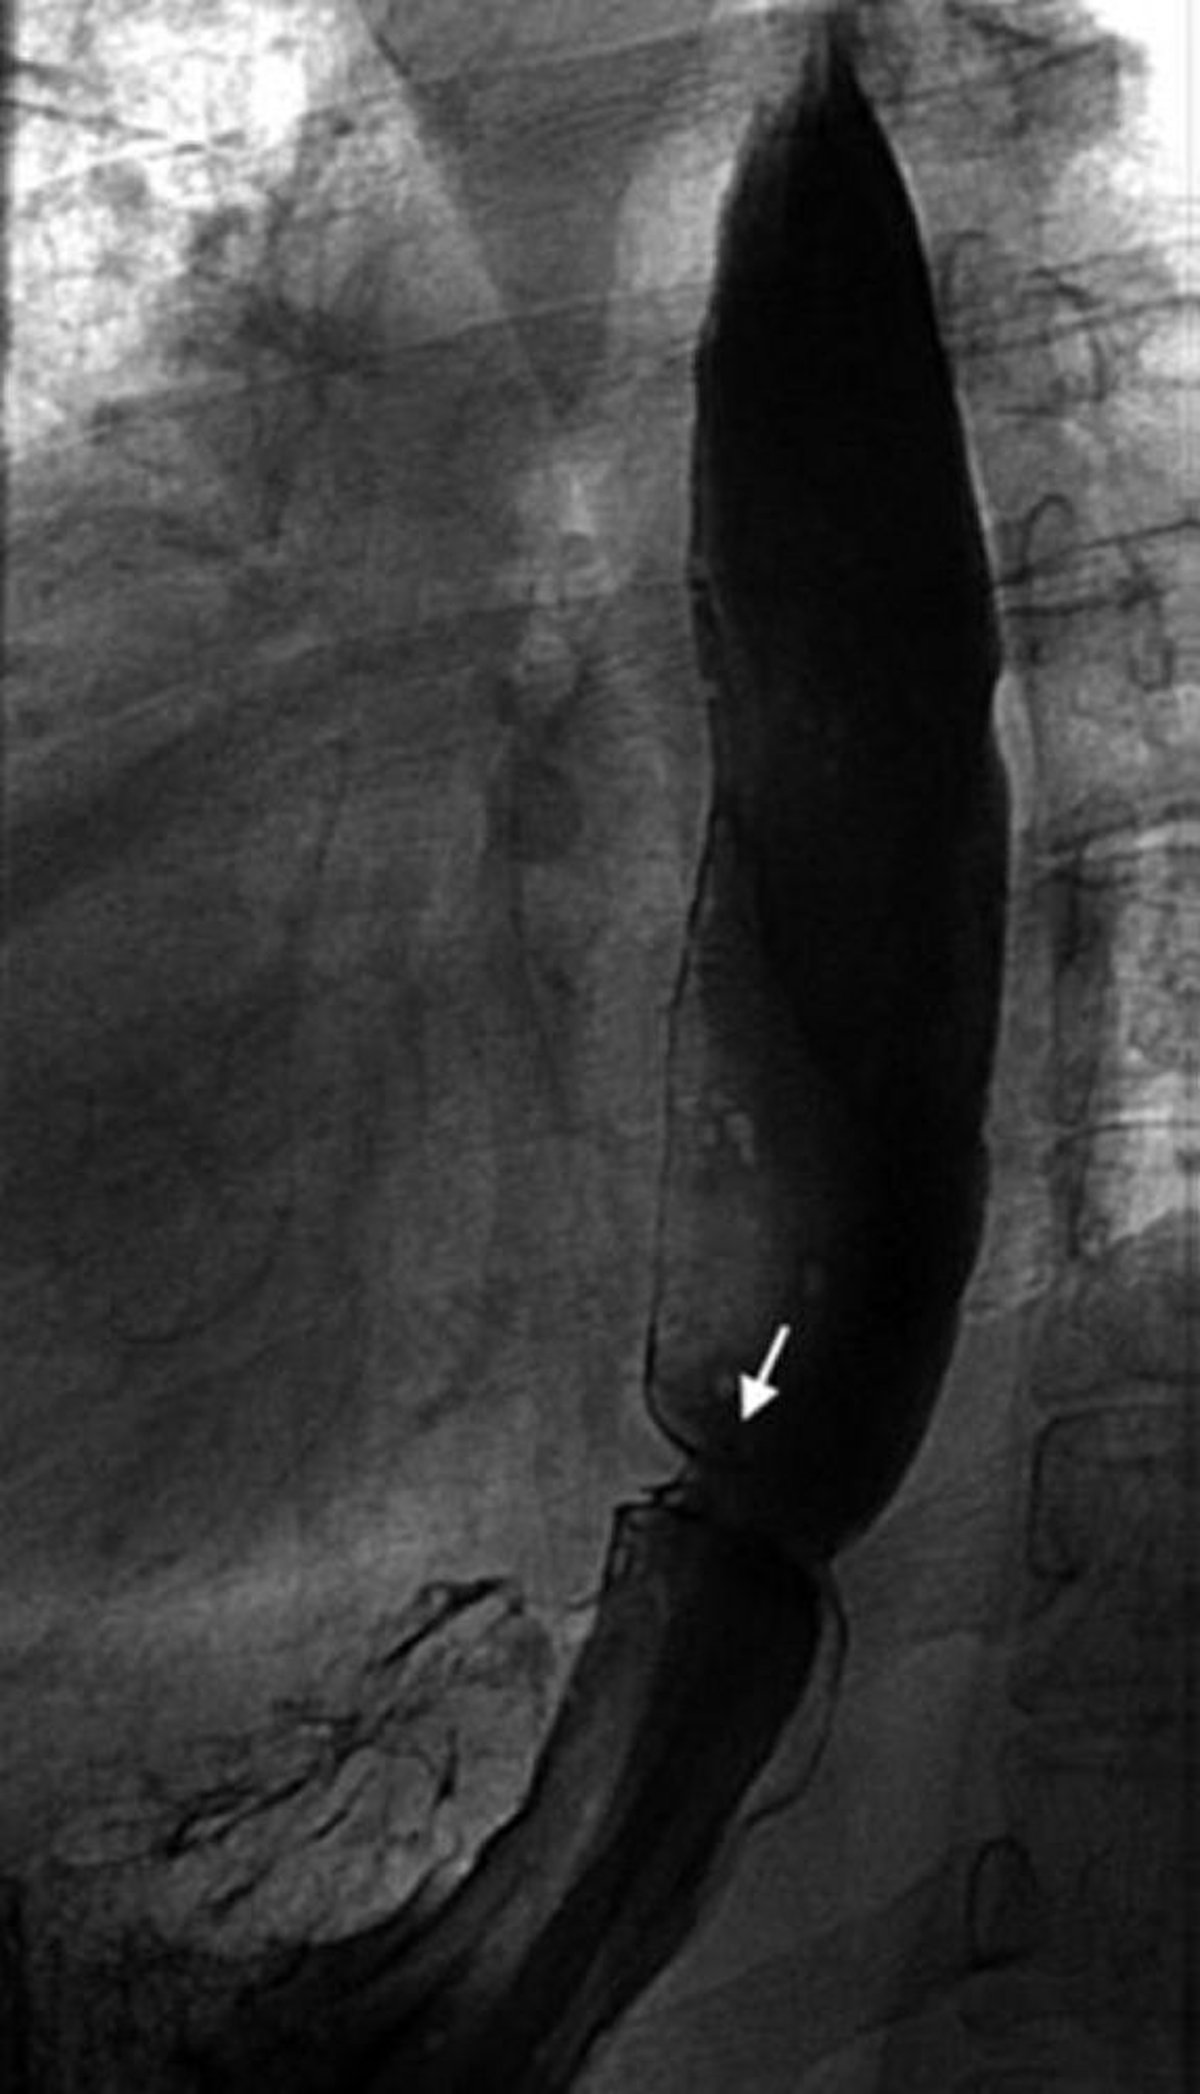

Pasto baritato che mostra un anello esofageo

Questa immagine mostra un anello di Schatzki (freccia).